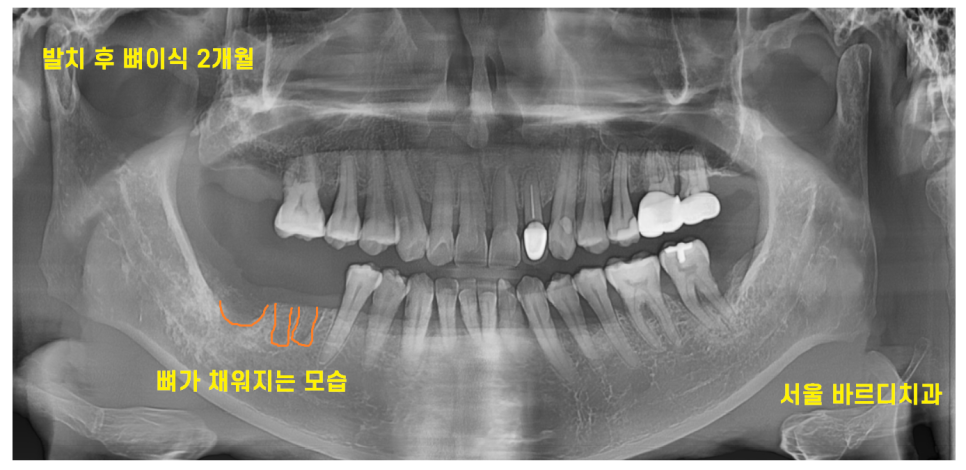

23.10.27

발치 후 뼈이식 2개월 된 사진입니다.

아직 x-ray 검사에서 웅덩이 진 모습이 보이네요.

조금 더 기다려야겠습니다.